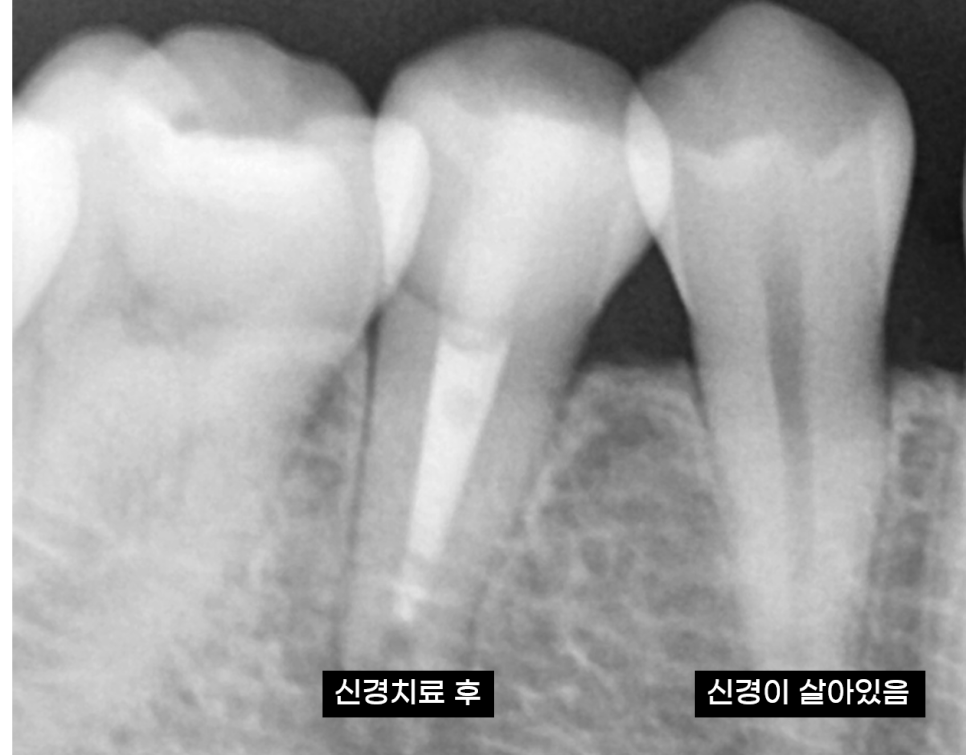

240305

신경치료 후 신경이 제거되면

혈액순환이 멈추게 되면서

치아가 까맣게 멍이든 것처럼 색이 변할 수 있습니다.

231211 치아에 그라데이션 처리 한 것 처럼 보이네요~

처음부터 까맣게 변하게 되지는 않습니다.

흰색 -> 회색 -> 갈색 -> 까만색